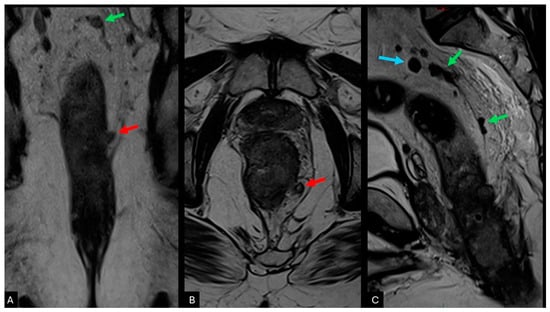

2.4. Tumour Deposits (N1c)

| Tumour deposits (N1c) | Tumour deposits follow the course of a venous channel compared to lymph nodes which are usually isolated within the mesorectal fat |